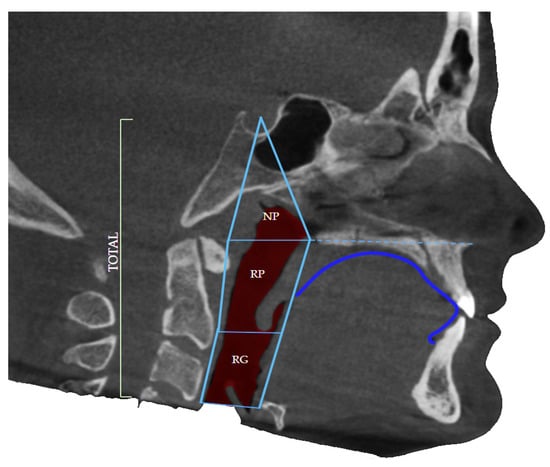

The upper border of the airway was defined by the diagonal line connecting the anatomical point of Sella Turcica and the posterior nasal spine (PNS). Sella turcica of pituitary (hypophyseal) fossa is a midline, dense structure in the sphenoid bone, which houses the pituitary gland. The posterior nasal spine represents the most posterior point of the maxillary line and nasal floor seen on the lateral projection of the CBCT of the patient (Figure 2).

The lower border was defined as the base of the epiglottis, the soft tissue that leads air further into the lungs, dividing the upper respiratory system from the lower, as well as the respiratory system from the digestive system. The borders were defined by the study by dos Santos et al. in 2020 during their trial to correlate airway volume and maximum constriction area location in different dentofacial deformities [1].

The level of constriction was determined by the level of the cervical vertebrae (CV), again using the CBCT of the patient in the section of airway in the software Invivo Anatomage. The cervical vertebrae can be divided into three parts, the upper border, the middle, and the lower border. Each of the cervical vertebrae can be divided into these three levels and the constriction of the airway can be defined accordingly. The most common borders where airway constriction is found are the middle border of CV2, the upper border of CV3 the Middle of CV3 as well as the lower border of CV3.

Figure 2. Defined borders of the airway volume consist of the nasopharyngeal (NP) portion as well as oropharyngeal regions: retropalatal (RP) and retroglossal (RG) and dorsum linguae identification.